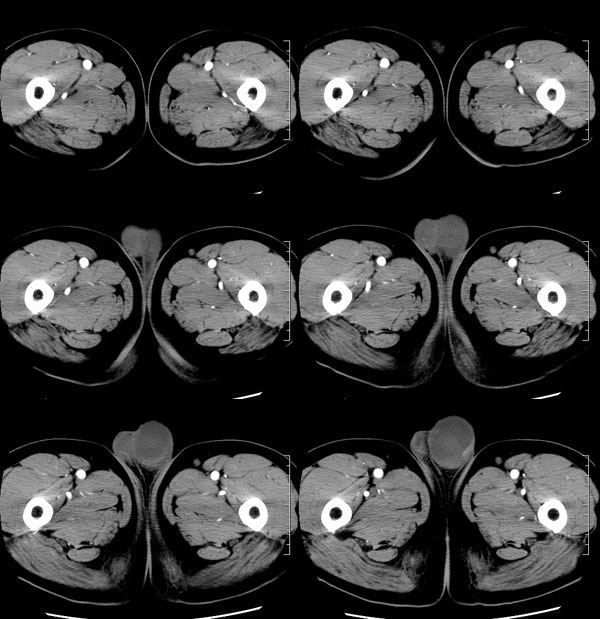

| 男性,69岁。自2个月前开始无意中发现左侧阴囊内一鸡蛋大小肿物,当时无伴疼痛等不适,未予重视。肿物逐渐增大,近段时间常伴左会阴部、腹股沟区牵扯不适,并于2周前在我院门诊行彩超检查提示“左侧附睾肿瘤可能,左侧睾丸鞘膜积液”。 专科检查:左侧阴囊肿大,其内可触及一鹅蛋大小肿物,表面光滑。肿物前部呈囊性感,后部质硬,按压无疼痛,无缩小,活动度良好。左侧睾丸未触及,透光试验(±)。                 王仕学发言:左侧睾丸见一密度不均肿块,边缘清楚,周围见水样密度影;考虑睾丸生殖细胞性肿瘤可能性大. 睾丸肿瘤占生殖系统肿瘤的3%-5%,占男性恶性肿瘤的0.5%-1.0%,其中生殖细胞性肿瘤占95%.睾丸肿瘤包括生殖细胞和非生殖细胞肿瘤两大类,前者占95%以上,后者不到5%.非生殖细胞肿瘤虽少见,但种类繁杂,主要有支持细胞、间质细胞和支持细胞-间质细胞瘤等功能性肿瘤,和间皮瘤、腺癌、横纹肌肉瘤、粘液性囊腺瘤、纤维上皮瘤、黑素神经外胚瘤、淋巴瘤等附属组织肿瘤。不同的病理类型的睾丸肿瘤发病率高峰不同,睾丸癌多发于35岁以前,精原细胞瘤发病高峰为30-35岁。精原细胞瘤约占睾丸肿瘤的60%,发病高峰在30-35岁。85%的患者睾丸有明显肿大,肿瘤局部侵犯力较低,肿瘤一般有明显界限。 手术:行“左侧附睾、睾丸、精索切除术”。 病理诊断:(左睾丸、附睾)肿物,为低分化腺癌。另送检(左精索远端)肿物,镜下亦为低分化腺癌。 免疫组化:ck(l)(++++)、cea(+++)、ca19-9(-)、psa(-)、plap(-)、p53(-)、vimentin(-)。 原贴地址:http://www.radinet.com.cn/forum_view.asp?forum_id=4&view_id=30707 |